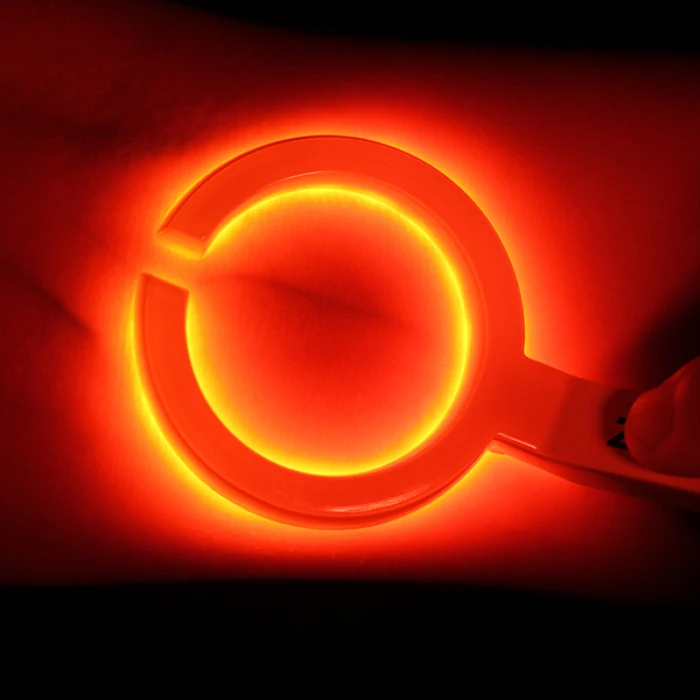

Взрослая детская визуализация инфракрасный васкулярный IV вены Finder Transilluminator вены просмотра TN88

Наше портативное устройство для просмотра Вены-Доступный портативный обнаружитель вен для общего доступа вены у взрослых и детей.

Питание от зарядного устройства непосредственно при использовании с 15 светодиодами, управляемыми одним переключателем.

Он используется для эффективного доступа IV в аварийной медицине.